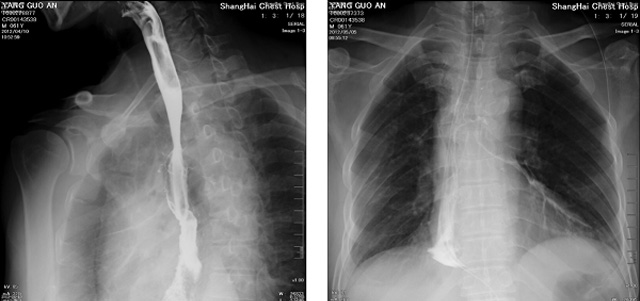

DR設備在2020年的新冠疫情中,加速了市場調整。以醫院為主的向二三級市場轉變。特別是小巧靈活的移動DR設計,填補CT和磁共振不能三維檢查的缺點,滿足內科外科特別是骨科的影像診斷需求。還有懸吊DR設備CT斷層射線系統。使用錐束成像技術對整個脊柱和整個下肢進行了體積三維掃描。無需使用對比劑,即可使用X射線呼吸功能標測來模擬模擬氣流和血流,以評估患者的肺動脈血栓。

數字化X線攝影依然是患者初篩的關鍵一環。靜態DR限制于探測器平臺。只能進行簡單普通的數字化影像檢查。胸部的疾病沒辦法篩查出微小的病灶。這樣導致DR慢慢的被CT跟磁共振代替。這樣造成了原來配套的數字化影像DR設備的 閑置。所以DR需要跟CT融合擴大DR的檢查使用場景。為DR提高更多的市場價值。X射線技術的原始形式和面向未來的可能性打破了CT成像和DR成像掃描技術之間的限制。融合成像趨勢更加明顯,多峰成像趨勢發展更加迅速。